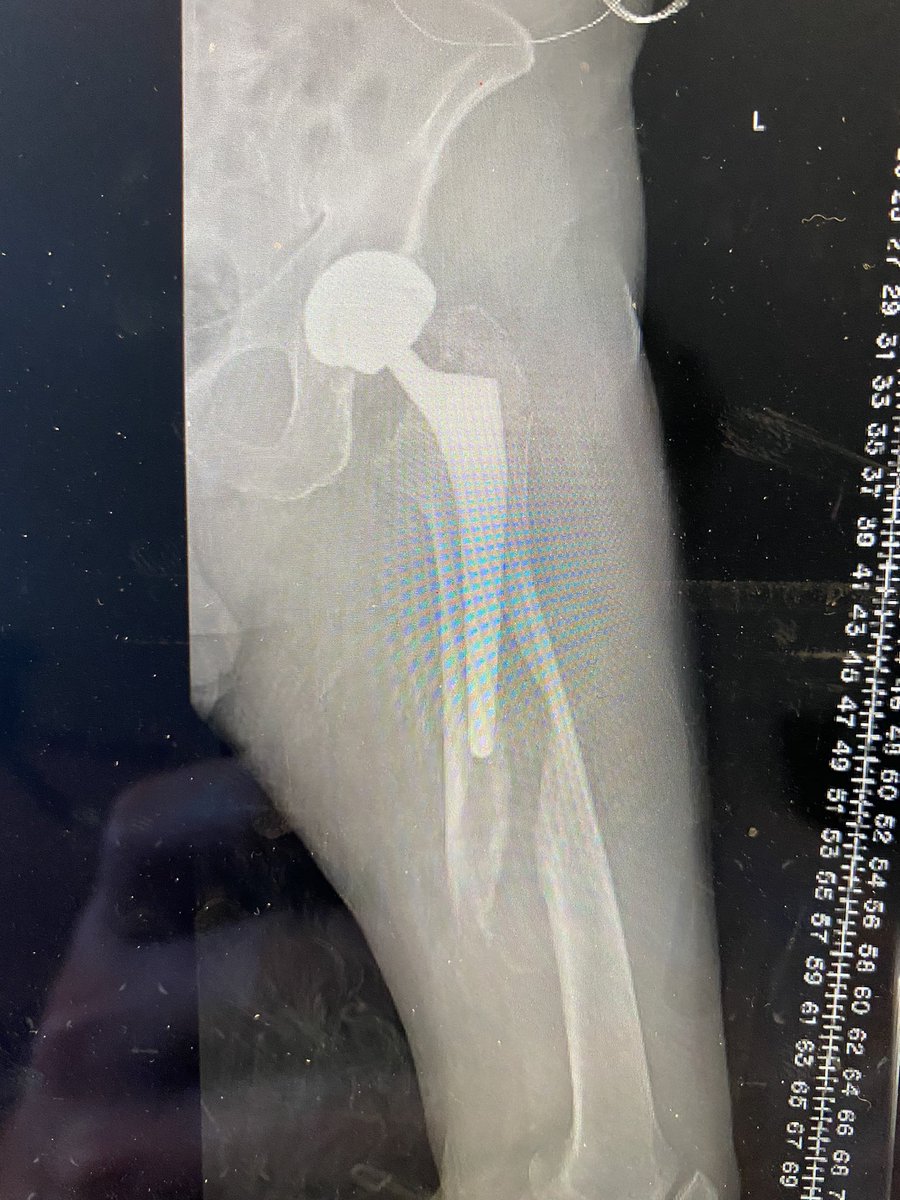

Thanks again @RiveraSurgical for incredible instruments. 5mins extraction and another no osteotomy day. Chronically infected left THA now with articulating spacer. Original surgery from DA approach so same approach used today. #orthotwitter #dofellowsneedETO’s